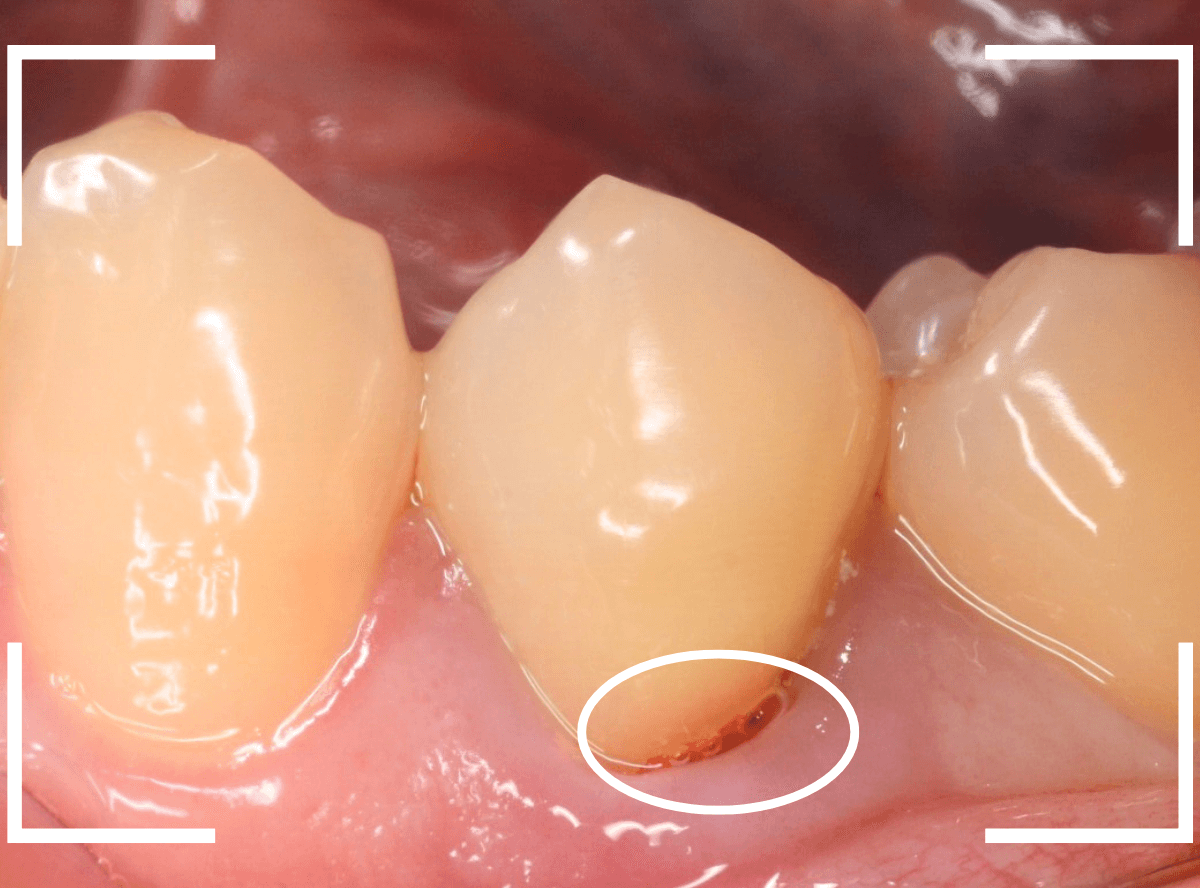

もう一度歯を確認すると、つけ根がうっすらと虫歯っぽいです。

これかな?しかし、風をかけてもしみません。

患者さんに状況をお話しし、麻酔をして慎重に歯を削って調べてみると、神経まで達する虫歯でした(><)

これが痛みの原因で間違いなさそうです。

しみるなどの症状が出る事なく、歯の側面が神経まで達する虫歯になる事は珍しいです。